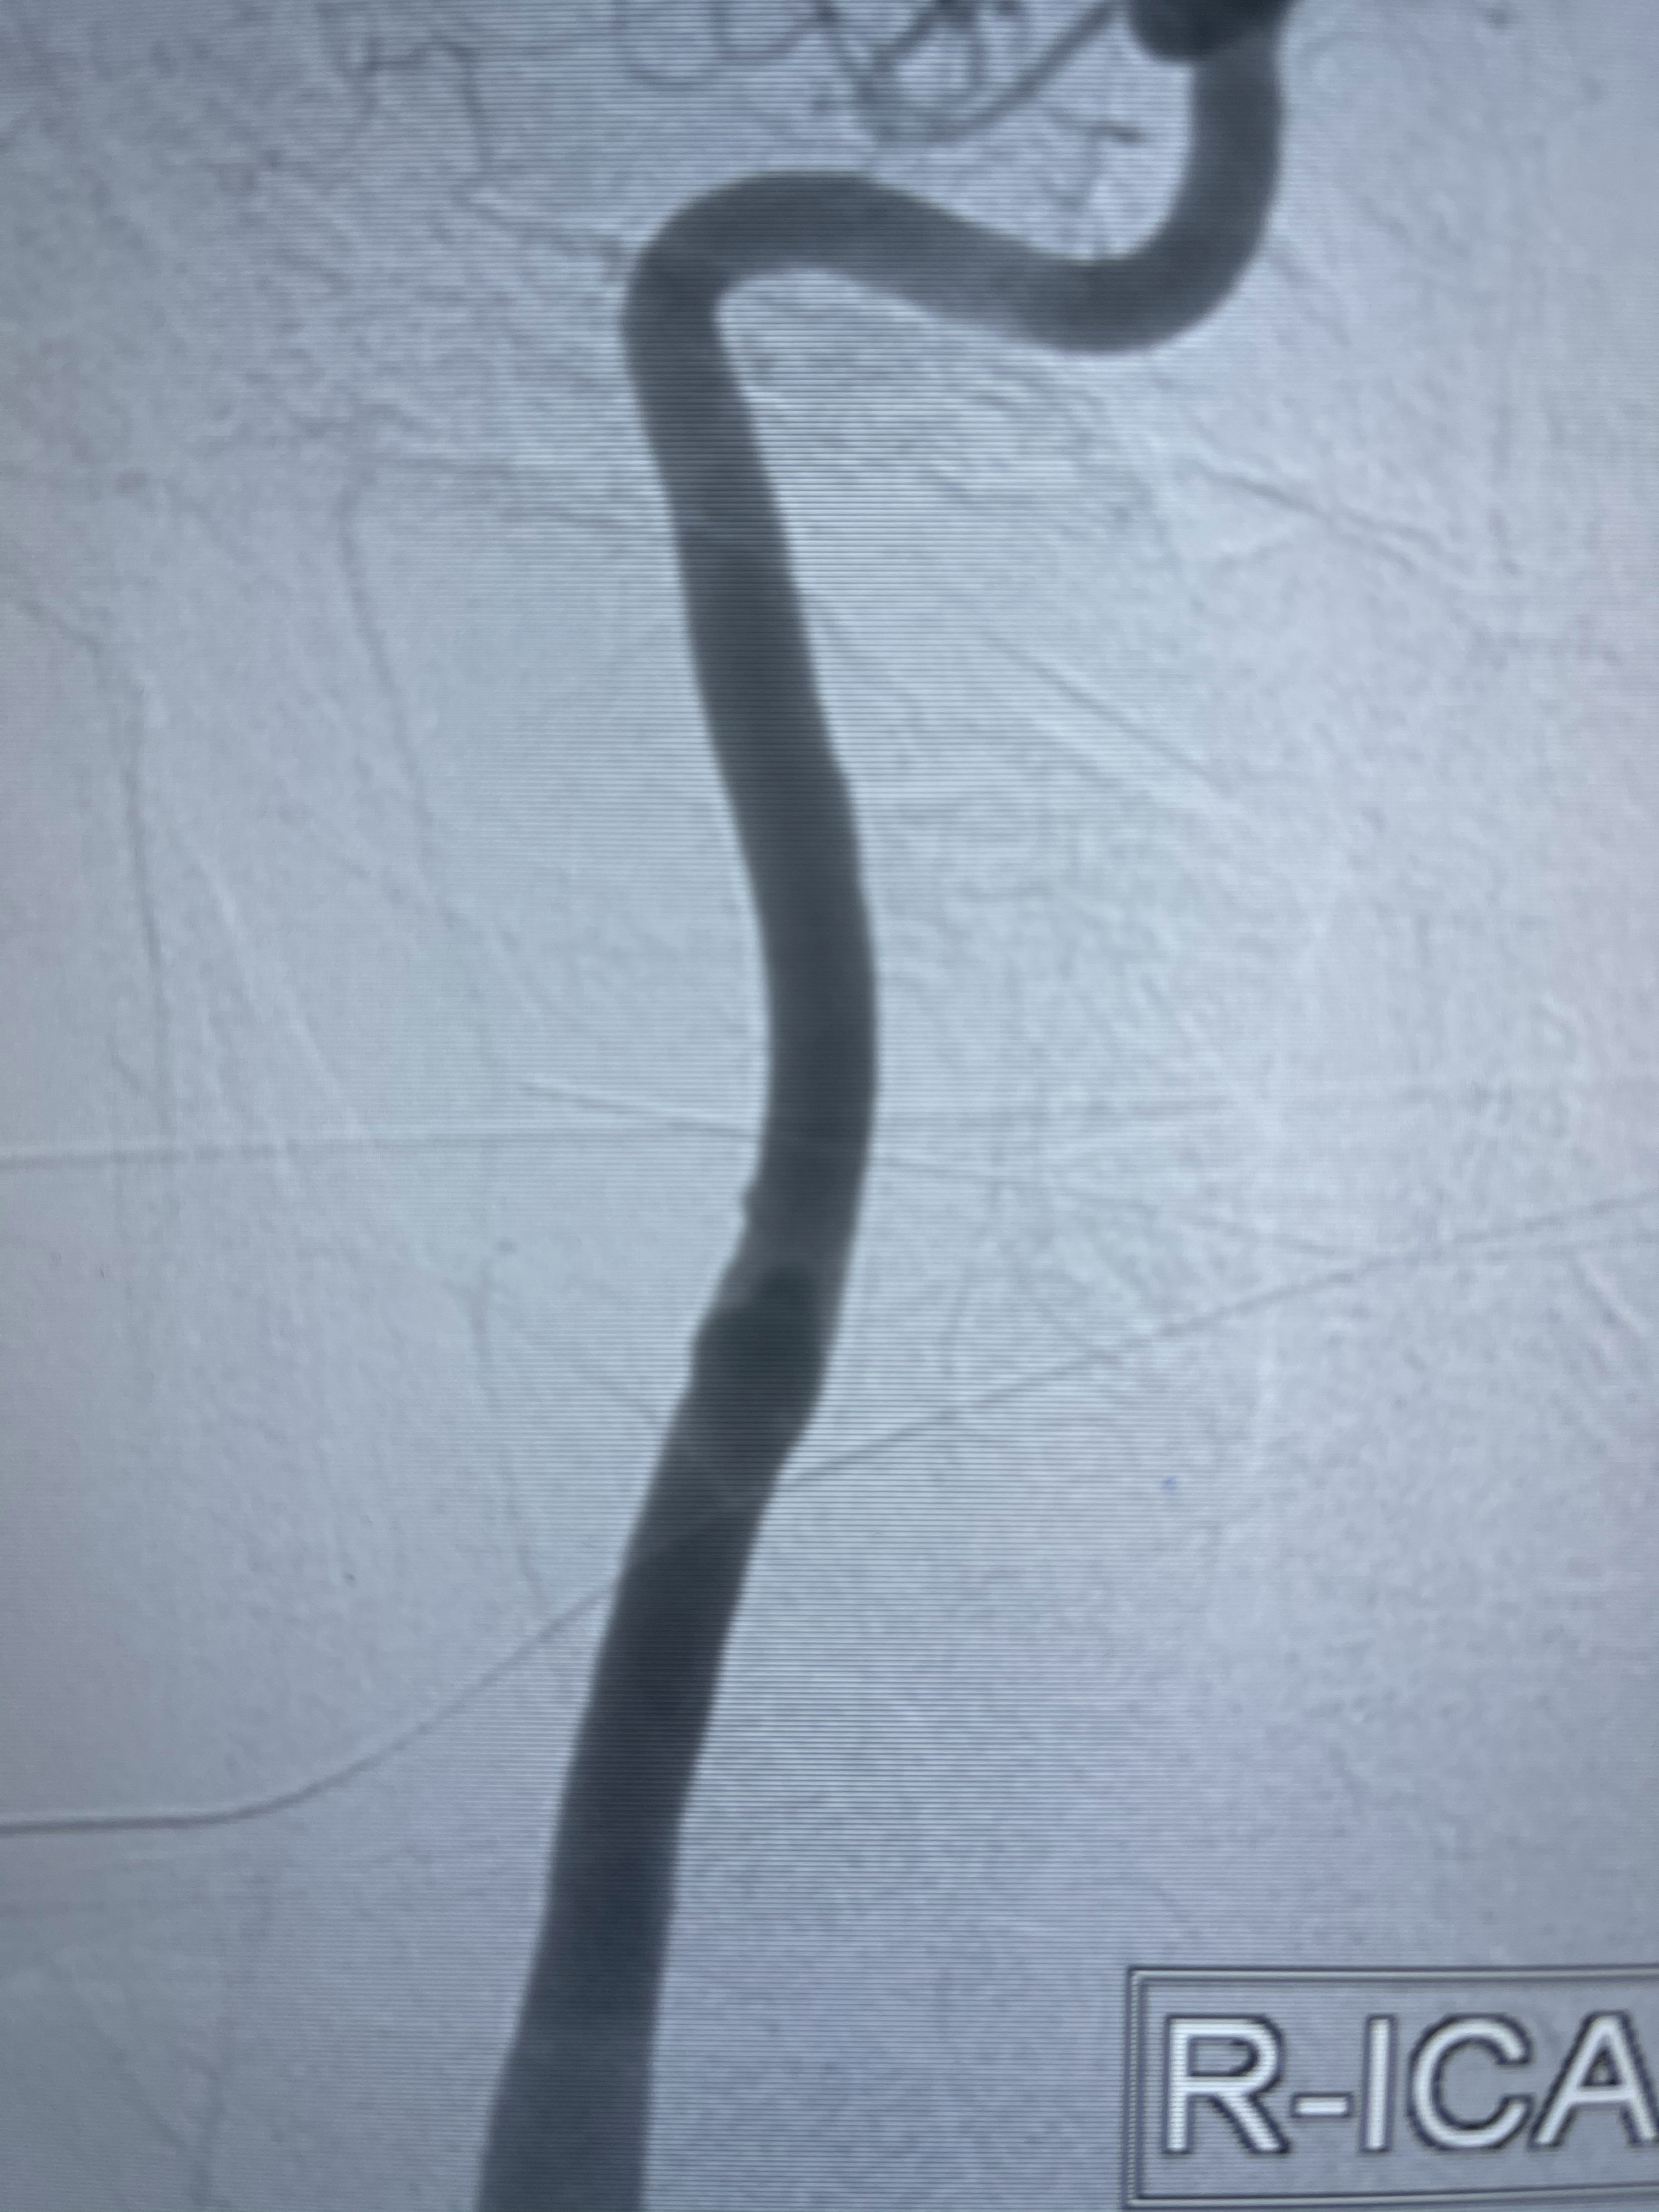

右侧颈内动脉夹层动脉瘤Lvis5.5-20mm支架辅助栓塞

支架到位

支架释放,透视下